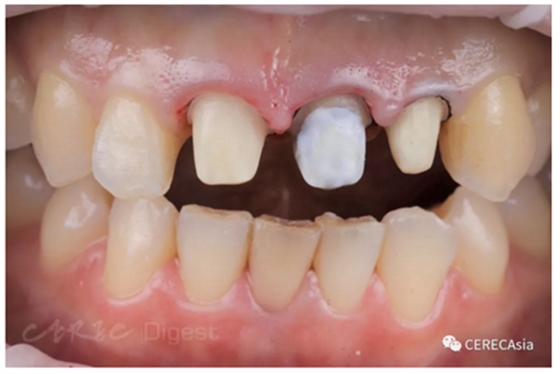

Sofia 馬上就要拍婚紗,因此牙冠延長一個(gè)禮拜后就拆除舊牙橋并重新制作,無法等到牙齦、骨頭完全穩(wěn)定。#21 支臺(tái)齒根管治療完成多年而且有金屬根心柱,顏色較深,使用遮色樹脂。

圖三、遮色、排齦照。